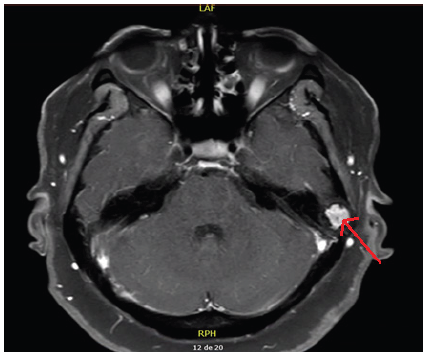

Como parte de su evaluación se pidió resonancia magnética nuclear con contraste de conducto auditivo interno (figura 1), encontrándose un nódulo sólido de bordes bien definidos entre la porción petrosa del hueso temporal izquierdo, sospechoso de un granuloma eosinofilico, metástasis u otros tumores.